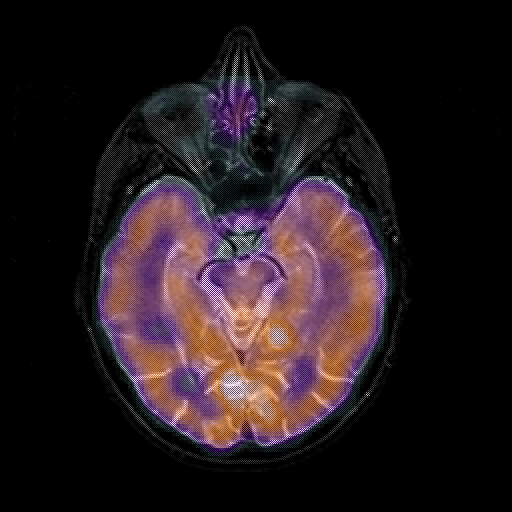

overlay 1: Slice 21

Slice 21

MRCBFCBF with

T1PDT2T1PDT2